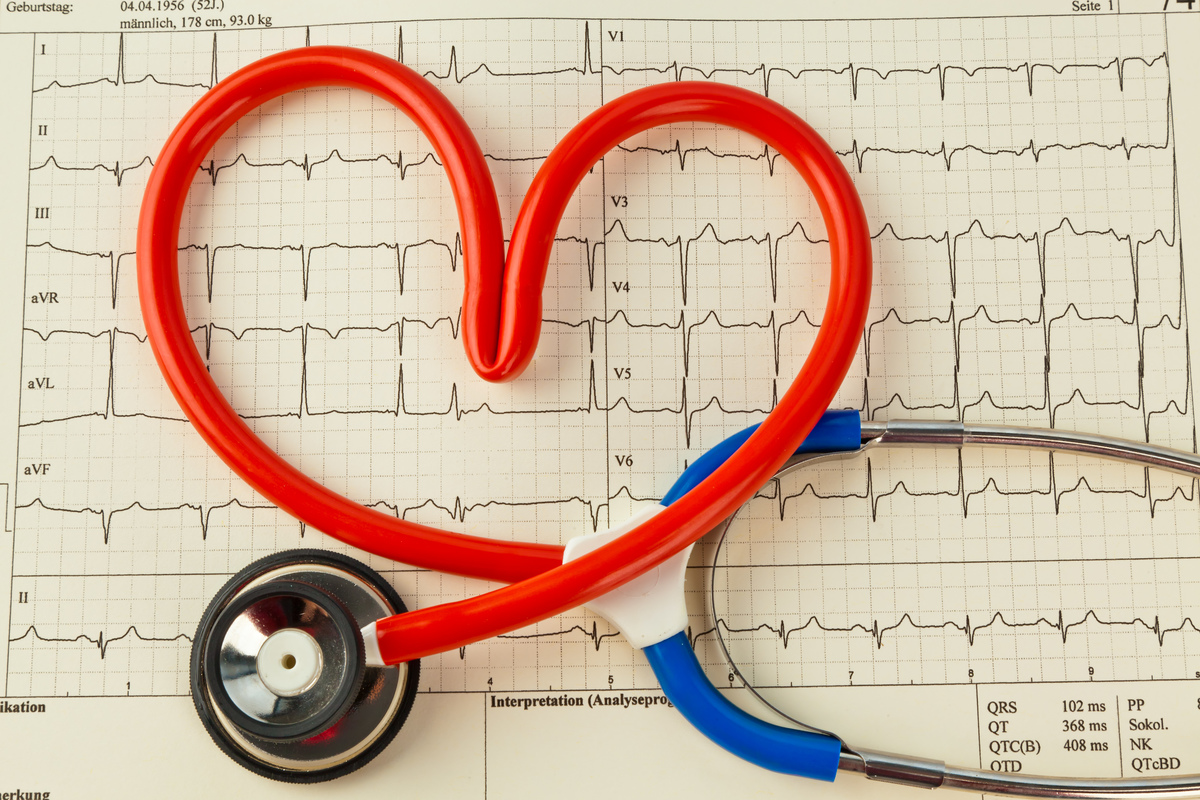

Check Your Blood Pressure Regularly

Blood pressure is called "the silent killer" because it doesn't produce symptoms. The American Heart Association recommends getting your blood pressure checked every two years. If you don't, you're putting yourself at risk for kidney disease. High blood pressure ruptures the blood vessels inside of your kidneys.

Once your blood vessels fail, your kidneys can't regulate blood pressure. Then, your blood pressure rises very quickly. Don't ignore your doctors' recommendations to get your blood pressure checked. It's quick and prevents several diseases.

Measure Your Blood Pressure Frequently

According to a scientific analysis in The Lancet, high blood pressure was the leading cause of heart disease in 2010. This condition leads to hypertensive heart disease, which thickens the heart and narrows the arteries. The American Heart Association asserts that avoiding high blood pressure "should be a healthcare priority."

If you don't have high blood pressure, work to prevent it. Checking your blood pressure once a month or even once a year can help. A 2015 study in The New England Journal of Medicine reports that the risk of heart disease lowers with a blood pressure of 120 mm Hg or less.

Don't Assume That You’re In The Clear

If you haven't had a blood pressure, cholesterol, or blood sugar check-up in a couple of years, you’ve waited too long. The American Heart Association recommends getting your blood pressure checked once a year since symptoms don’t appear in most people. Blood glucose should be measured every three years, and cholesterol should be monitored every four to six years.

"Don’t assume you’re not at risk," advises Dr. Robert Ostfeld, director of preventive cardiology at Montefiore Health System. If your cholesterol or blood sugar levels aren’t in the normal range, you’ll need more frequent check-ups and possibly medication.